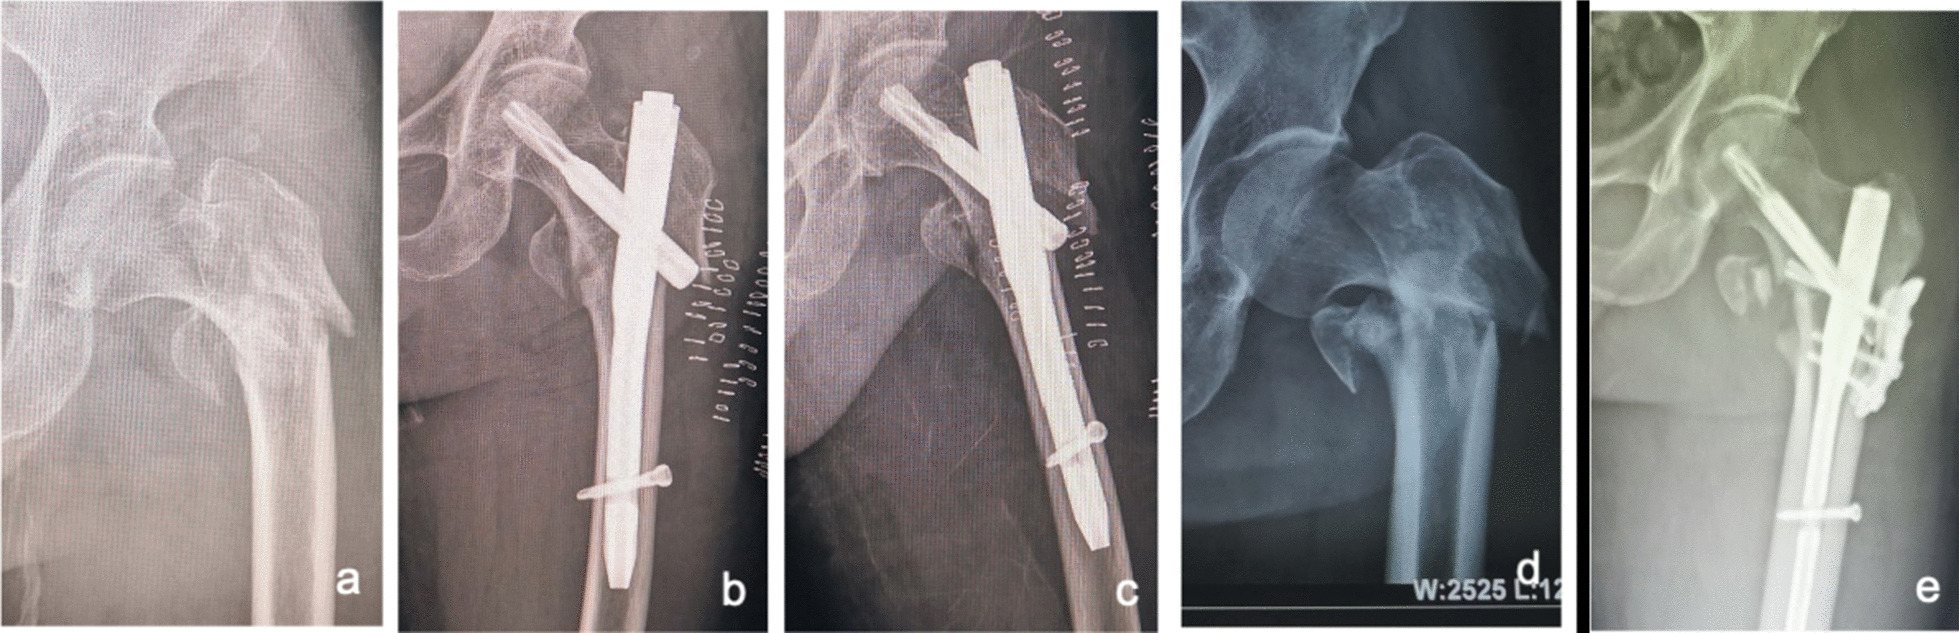

Cautions: ① Strong hip limb muscles can lead to deformity and displacement of the fracture, which is sometimes problematic for bone tenaculums to counter. The large working distance of the pelvic resetting forceps facilitates counteracting the powerful perihip muscles. In addition, the blunt tip of the pelvic reduction forceps is less likely to cause collateral damage. For this reason, we routinely prepare pelvic reduction forceps or fracture clamping forceps preoperatively, and when traction reduction is difficult, an anterior approach with limited incision clamping is preferred for resurfacing and maintaining reduction, followed by intramedullary nailing. ② Irreducible intertrochanteric femoral fractures associated with the lateral wall (mostly reverse oblique intertrochanteric fractures) have a high rate of internal fixation failure [28, 29]. Even with good intraoperative clamping and reduction, sometimes the spiral blade of the intramedullary nail does not provide effective fixation of the lateral wall, and postoperative redisplacement of the lateral wall occurs (see Fig. 13a–c), so it is recommended that the lateral wall is reinforced at the same time as the intramedullary nail fixation (see Fig. 13d, e) to reduce the rate of fixation failure [29]. ③ The rate of difficult fractures at our center was 32.76% (115/351), which is higher than the previously reported rate of irreducible fractures in all intertrochanteric fractures (3–17%) [2, 4, 6]. In the analysis of the above literature reports, only AO/OTA types 31-A1 and 31-A2 were included, without including type 31-A3. However, most of the actual 31-A3 types are irreducible fractures [7]. In addition, the partial data of our group came from consultation cases in many hospitals due to difficulties in fracture treatment, so the proportion of irreducible intertrochanteric fractures was large, leading to a data bias. The high proportion of irreducible femoral intertrochanteric fractures suggests the importance of mastering the minimally invasive clamp reduction technique. ④ In extremely osteoporotic geriatric femurs, lateral wall blow-out fractures can occur while implanting nails. We can strengthen the lateral wall with the plate (Fig. 13d, e), application of circumferential cerclage cable [29], and suture with nonabsorbable suture, etc. ⑤ When determining the nail entry portal, it should be slightly more medial than the conventional site on the greater trochanter because due to the pushing effect of soft tissue, it is easy to eventually lead to the outer opening. The consequence of the outer opening easily leads to different degrees of hip varus and left lameness.

Fig. 13.

After the fixation of intramedullary nails in irreducible intertrochanteric femoral fractures associated with the lateral wall (mostly reverse oblique intertrochanteric fractures), the lateral wall is easy to displace again (a–c); lateral wall reinforcement can avoid redisplacement and improve fracture stability (d, e)